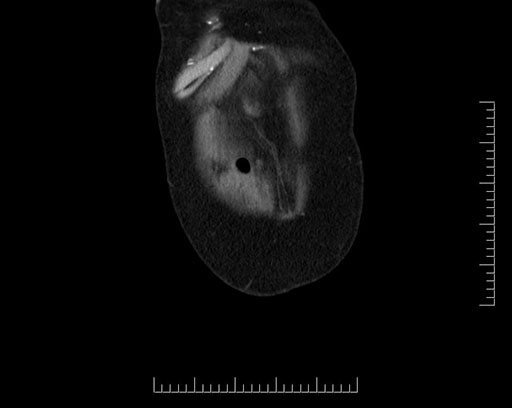

Coronal - stented